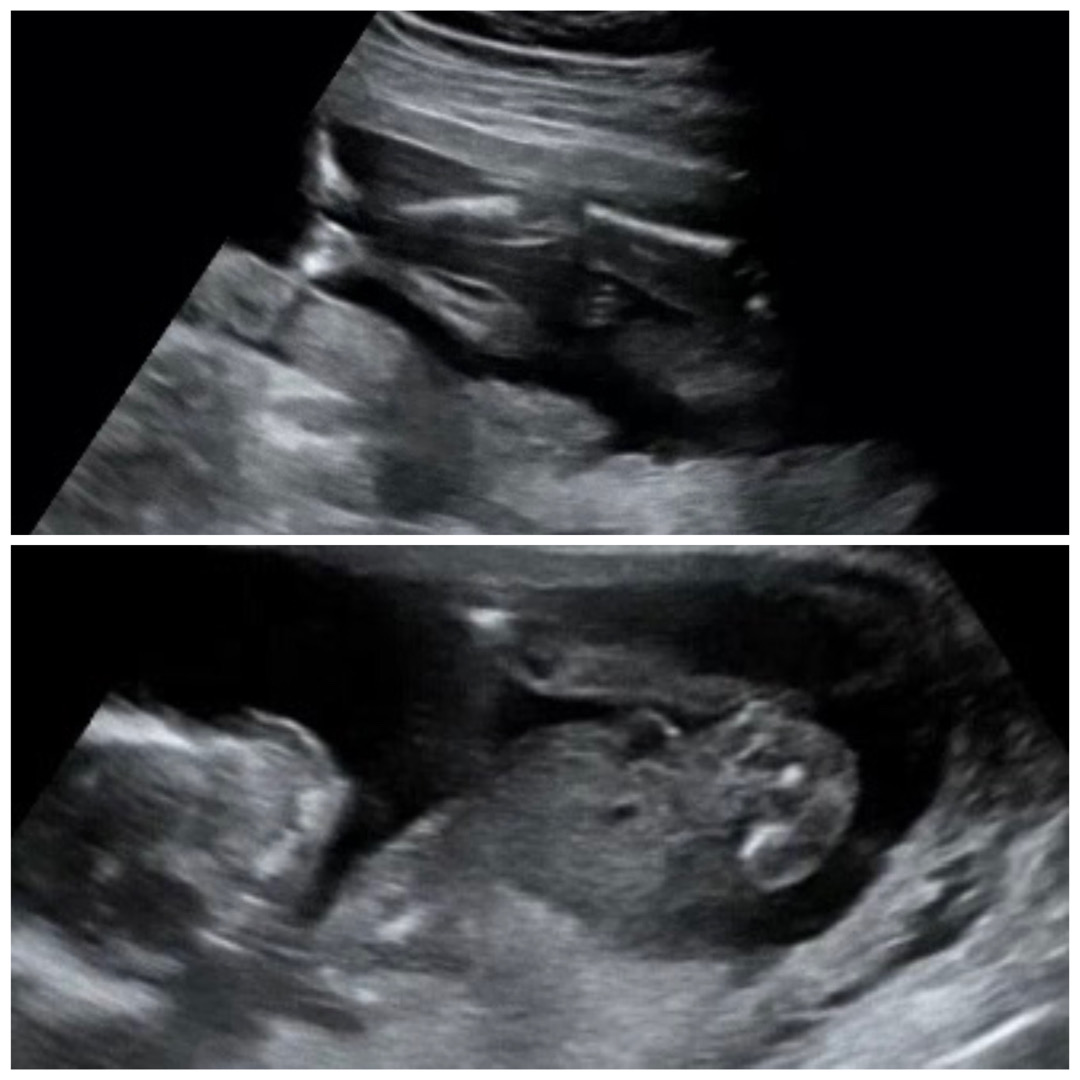

17주 2일차인데 성별 보기 실패했어용..

넘 궁금해서 기대하는 마음으로 갔는데 다리 사이에 팔인지.. 뭐가 있더라구요 흑흑😭

봐 주셔서 감사해용~~~ 이대로 딸맘 되는 건가용~~

헉헉~~ 딸이든 아들이든 전부 좋은데 그래도 궁금하네용 ㅎㅎ